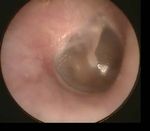

Which of the following is a sign of severe otosclerosis on otoscopy?

Quiz – Q2

Correct!

Schwartze Sign Myringosclerosis Middle ear effusion Acute Otitis Media

Schwartze sign: Increased vascularity on the

promontory that is seen through the tympanic

membrane. This indicates active otosclerosis.

Only seen in ~10% of cases. Proceed to Q3